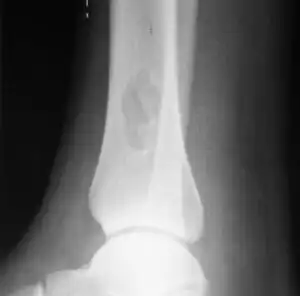

| X-ray of nonossifying fibroma of distal tibia. | |

Diagnosis is by X-ray or MRI, usually when investigating a person for something else.[3] Medical imaging typically shows a well marginated radiolucent lesion, with a distinct multilocular appearance, sometimes looking like bubbles.[3] It is usually around 1-2cm in size, but be as large as 7cm.[4] They consist of foci consist of collagen rich connective tissue, fibroblasts, histiocytes and osteoclasts.[3] Usually no treatment is required.[4] Surgical curettage and bone grafting may be required if it is large.[4]

It is usually iagnosed by x-ray or MRI, when investigating another problem.[1] The tumor presents as a well defined radiolucent lesion, with a distinct multilocular appearance, sometimes looking like a "soap bubble".[2] If small and no symptoms, then biopsy is not needed.[1]

1. a. Front view X-ray: NOF of the lower leg bone near ankle, with well-defined tumor

1. b. Side view X-ray: NOF of the lower leg bone near ankle, with well-defined tumor